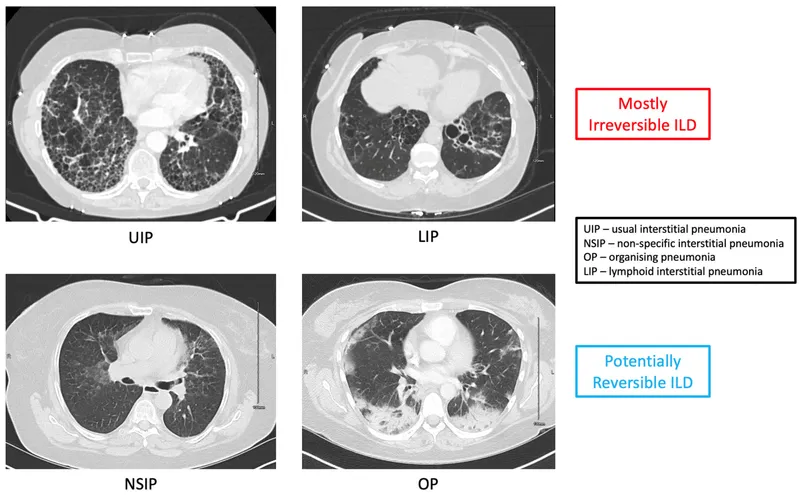

⭐ Usual Interstitial Pneumonia (UIP) is the hallmark radiologic and pathologic pattern of IPF, defined by bibasilar, subpleural honeycombing and reticulation. It carries the worst prognosis among the IIPs.

A group of diffuse parenchymal lung diseases of unknown cause, distinguished by specific histopathologic patterns.

- Histology: Usual Interstitial Pneumonia (UIP) pattern.

- CT: Bibasilar, peripheral reticulation with honeycombing.

Non-specific Interstitial Pneumonia (NSIP)

- Better prognosis than IPF; strongly associated with connective tissue disease.

- Histology: Temporally uniform inflammation or fibrosis.

Cryptogenic Organizing Pneumonia (COP)

- Formerly BOOP; excellent response to steroids.

- Histology: Masson bodies (granulation tissue plugs in alveoli).

⭐ The UIP pattern is the indispensable hallmark for diagnosing IPF, signifying irreversible patchy fibrosis and architectural distortion (honeycombing).

- Pattern: NSIP (Non-Specific Interstitial Pneumonia) is the classic finding.

- Pattern: UIP (Usual Interstitial Pneumonia) is the most common, mimicking IPF.

- Patterns: Can be NSIP or Organizing Pneumonia (OP).

- Sjögren's: LIP (Lymphocytic Interstitial Pneumonia) is characteristic.